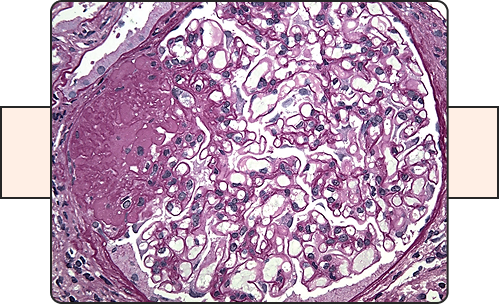

Membranous Nephropathy

This protocol aims at evaluating the efficacy of an investigational medication for adult patients with primary Membranous Nephropathy, in addition to evidence based standard of care aiming at reducing proteinuria and delay the progress of kidney disease.

IgA Nephropathy

This Protocol will evaluate the efficacy of an investigational medication for adult patients with IGA Nephropathy, in addition to evidence based standard-of-care medications aiming at reducing the proteinuria with the goal is to delaying the progression of kidney disease.

FSGS (Focal Segmental Glomerulosclerosis)

This Protocol will evaluate the efficacy of an investigational medication, in addition to evidence/based standard of care therapy aiming to reduce proteinuria and delaying the progression of kidney disease.